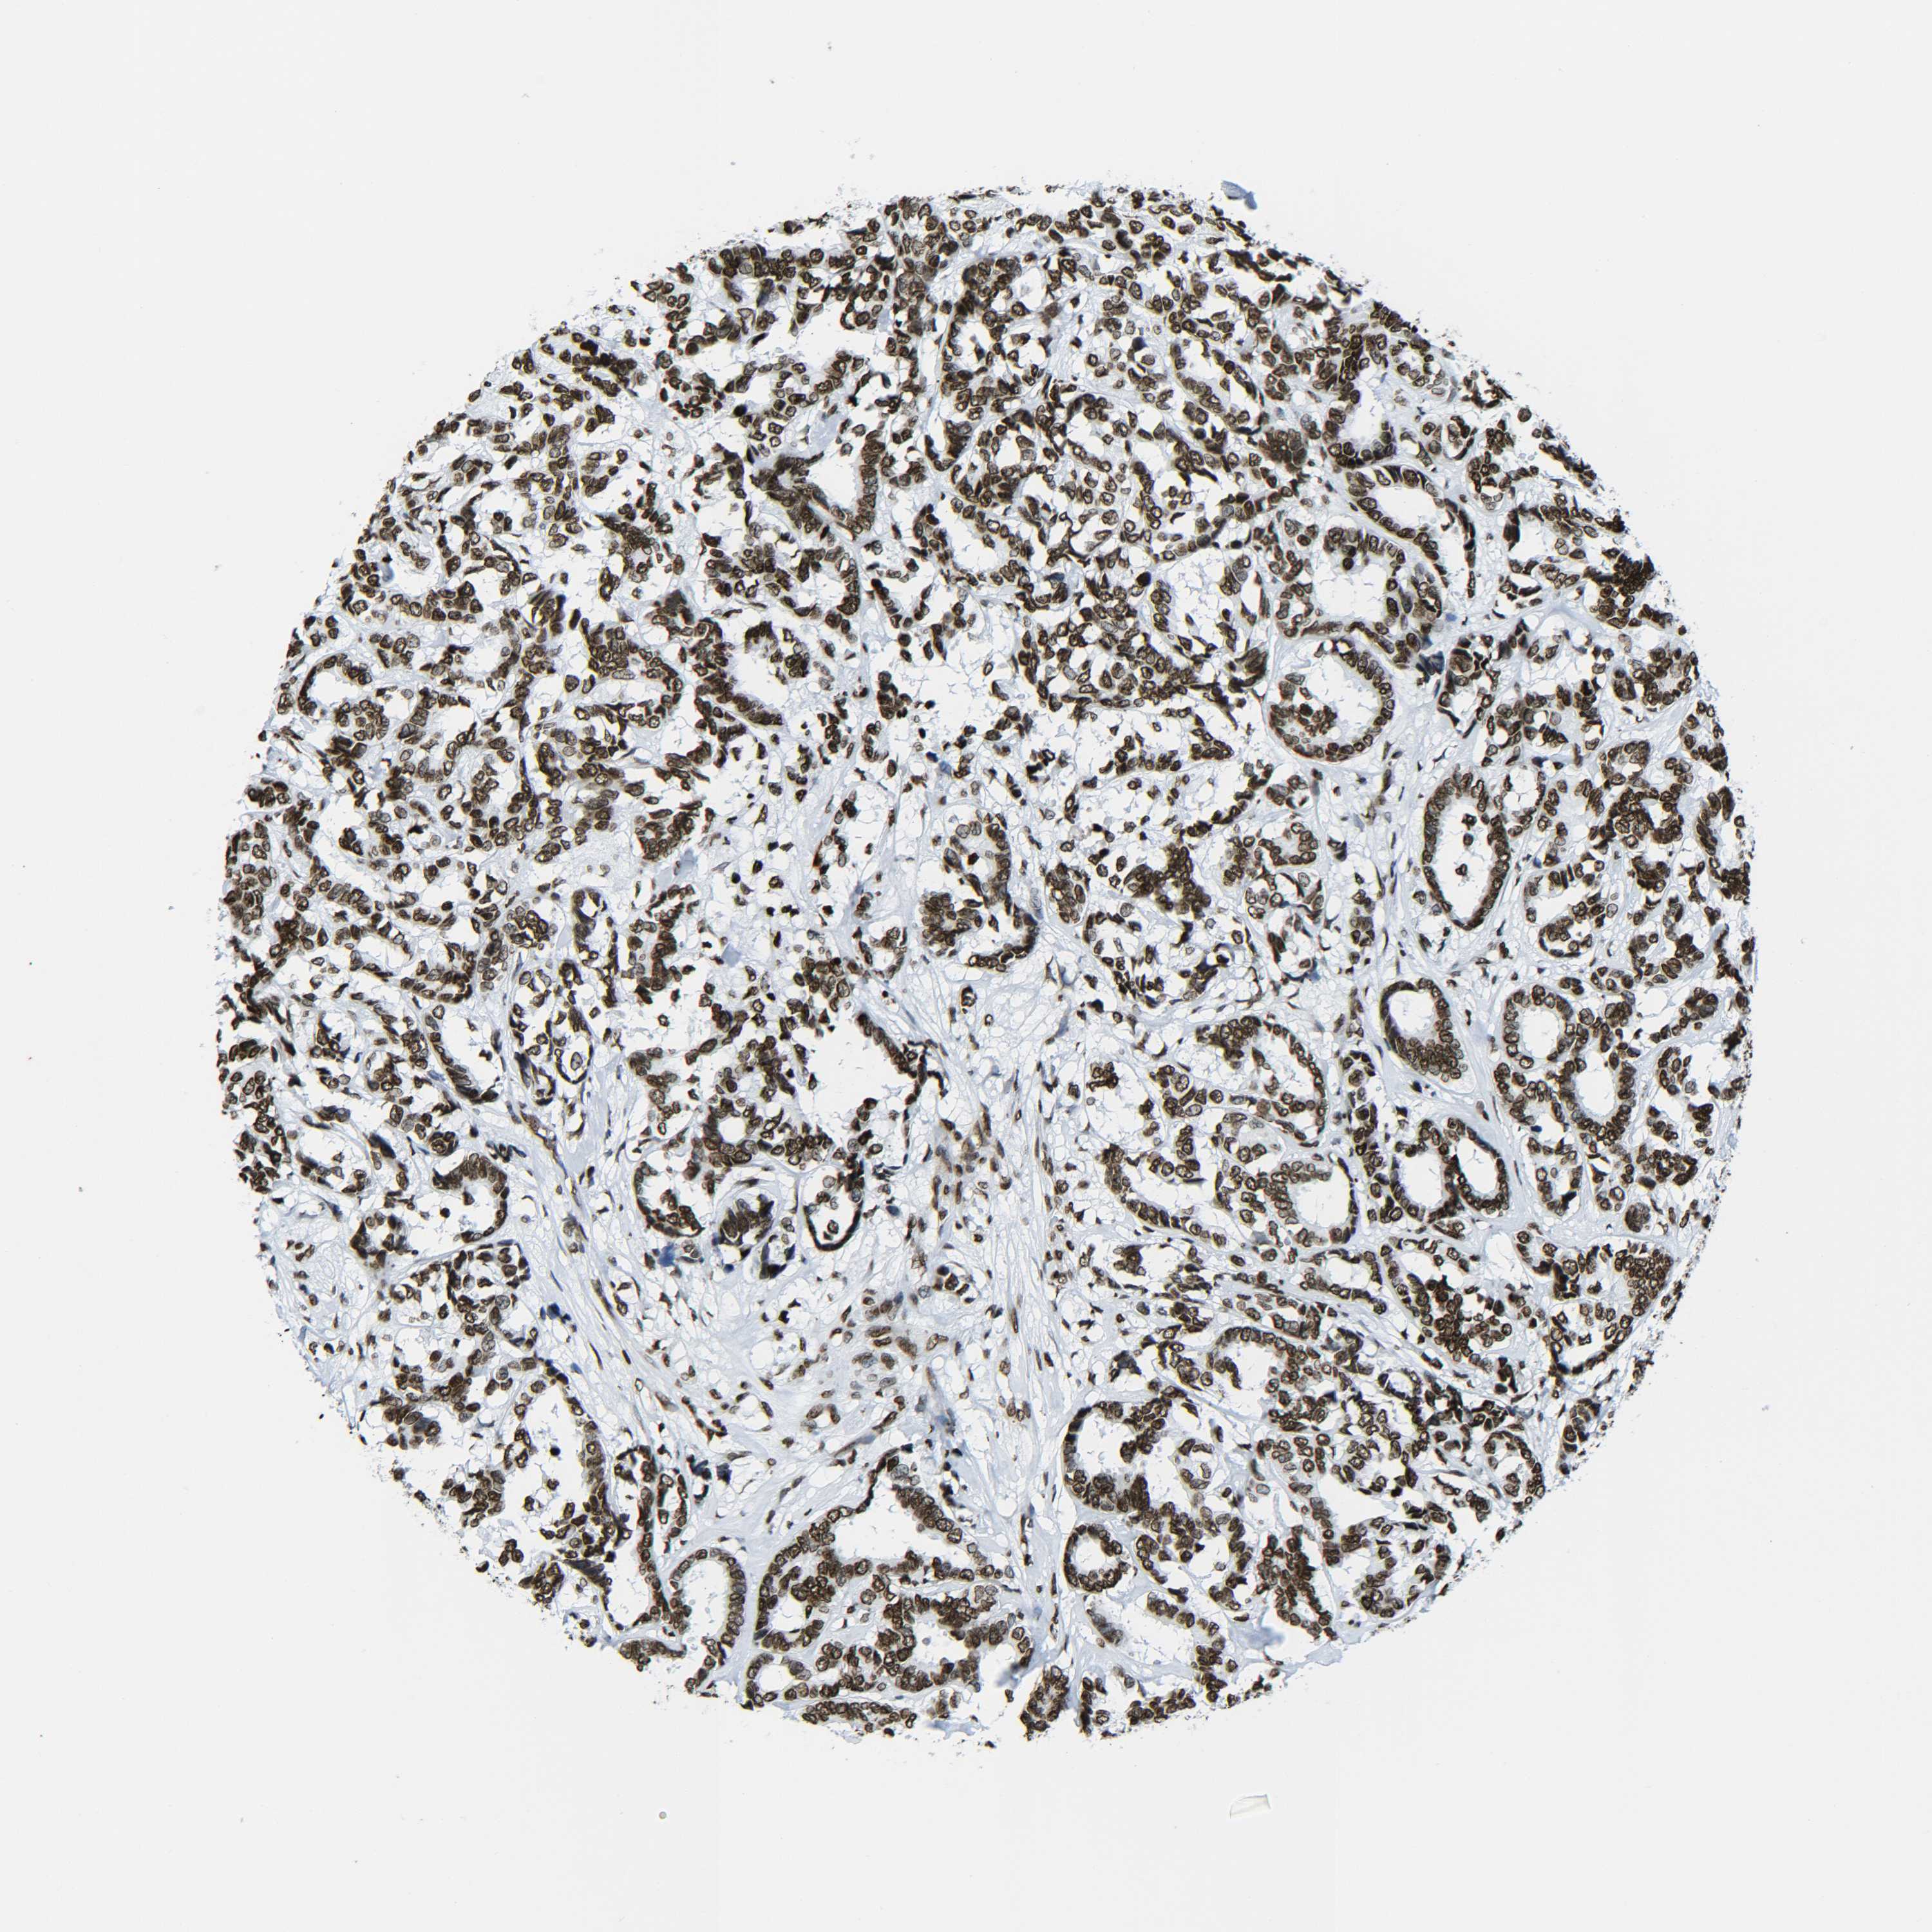

CANCER BREAST CANCER Show tissue menu

BRCA TCGA BRCA VALIDATION PROTEIN EXPRESSION